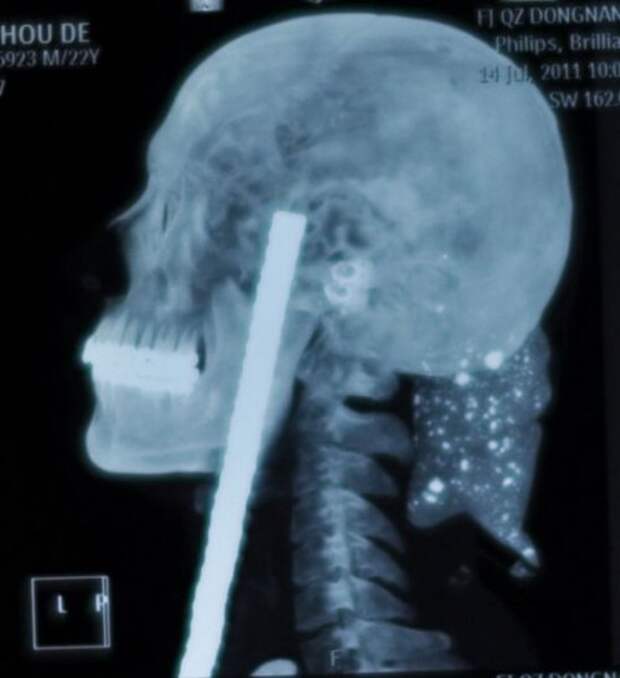

22-летний Ву Мод (Wu Moude), приземлился на стальную арматуру, которая на 15 сантиметров погрузилась в его голову под подбородком. Для извлечения потребовалась операция продолжительностью пять часов, во время которой хирурги разрезали трахею и череп Ву.